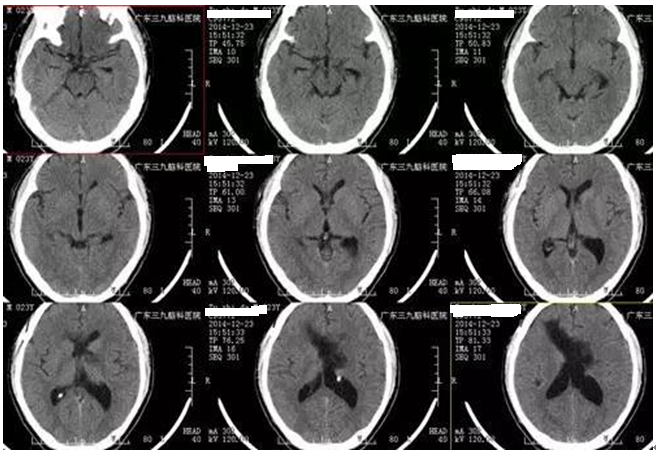

▲术后检查

在神经外一科张良主任主刀下完成手术治疗切除,术后系统支持和康复训练后,患者神志清楚,语言清晰,四肢活动自如。可喜的是经过系统康复恢复后,他仍可以继续运动生涯。术后病理诊断为脑室内肿瘤,符合中枢性神经细胞瘤诊断。8月随访情况,经过一年多的恢复,患者每星期能完成一百公里跑步训练,体能恢复和以前国家队的时候差不多了,患有巨大中枢神经细胞瘤的他,重新站在帆船赛场上,扬帆远航,劈波斩浪。